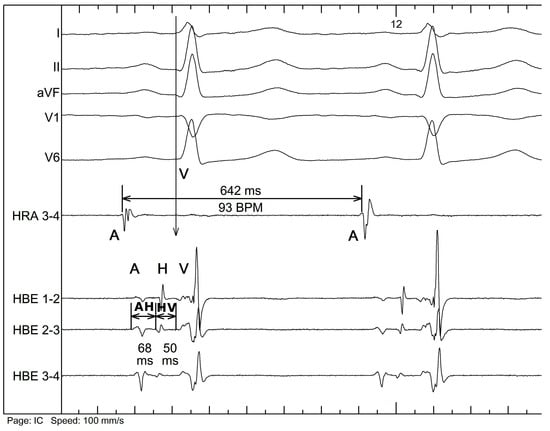

- AH interval, measured from the A to H signal—corresponds to the conduction through the atrioventricular node.

- HV interval, measured from the H to earliest V signal—corresponds to the conduction through the His–Purkinje system.

- AV interval, measured from the A to earliest V signal—corresponds to the total atrioventricular conduction.

- AA interval, measured from the A to A signal of the consecutive cycle—corresponds to the interval between consecutive cardiac cycles, the equivalent of the heart rate.